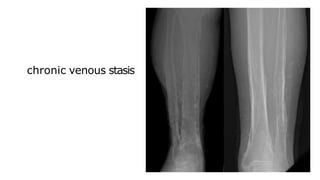

Multiple periosteal reactions

3) Venous stasis and ulceration of the legs

chronic venous stasis